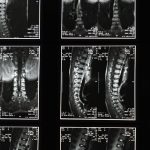

Décompression neurovertébrale : une solution naturelle pour soulager les douleurs dorsales réfractaires

La décompression neurovertébrale est une méthode innovante et efficace pour soulager les douleurs liées à la colonne vertébrale. Cependant, pour maximiser les résultats et prolonger les bénéfices obtenus durant le traitement, il est crucial d’effectuer des ajustements posturaux. Ces ajustements aident non seulement à maintenir une posture correcte, mais aussi à prévenir la réapparition des maux de dos et des douleurs cervicales. Cet article se penche sur les ajustements à mettre en œuvre pour conserver l’efficacité de la décompression neurovertébrale.

La décompression neurovertébrale est une méthode non invasive qui a révolutionné le traitement des douleurs liées aux troubles vertébraux, permettant d’alléger la pression sur les nerfs et ainsi de favoriser un mieux-être durable. Cependant, pour prolonger les bénéfices de cette technique, il est crucial de mettre en place des ajustements posturaux appropriés. Ces ajustements permettront de maintenir l’alignement corporel optimal tout en facilitant le processus de guérison.